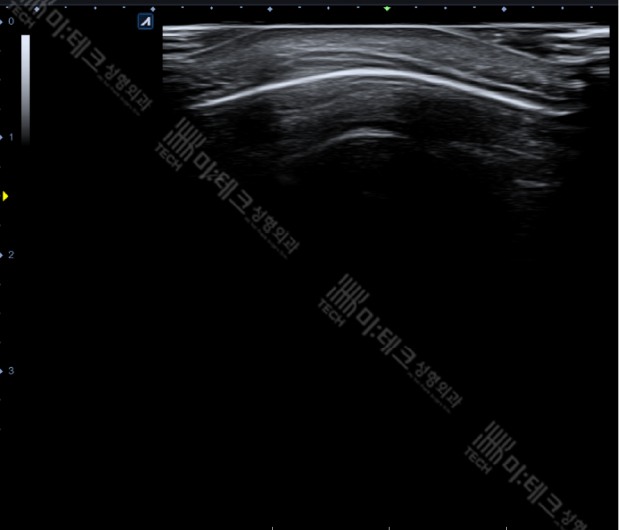

뼈 위, 근육 아래에 비정상적인 음영이 관찰되네요.

뼈가 튀어나오지 않음을 확인했습니다.

아주 깊숙하게 있는 덩어리이기 때문에 점만 찍어서 수술하기는 어렵습니다.